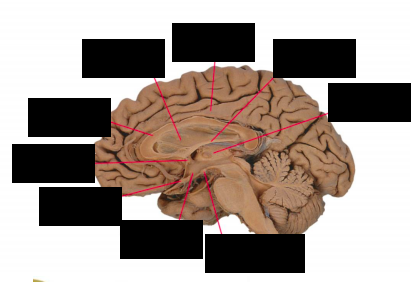

What structure in the brain is vital for fine motor control and is often connected to Parkinson’s?

Substantia Nigra